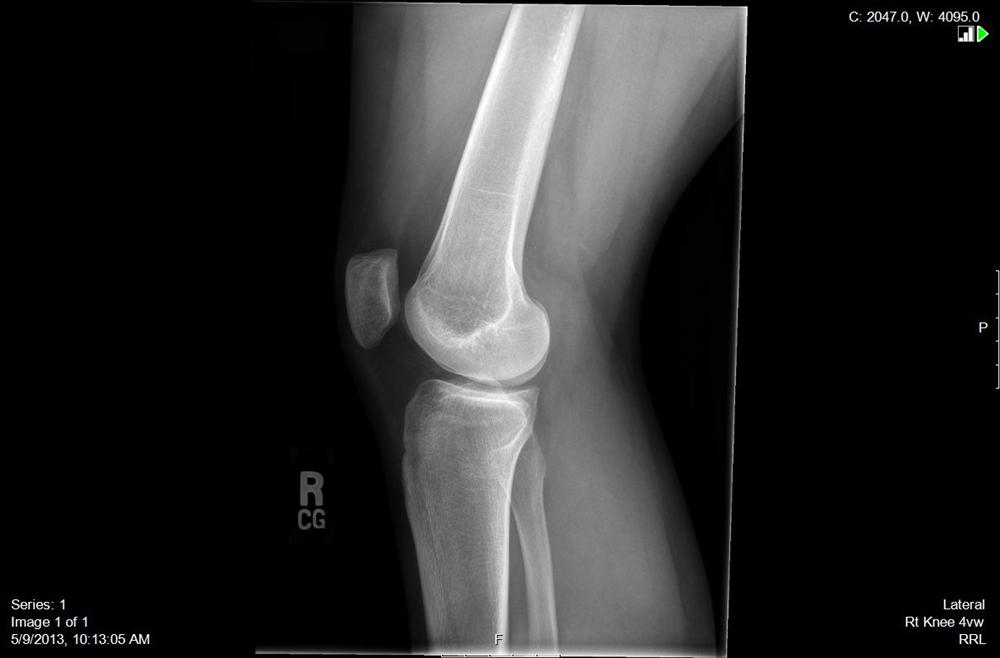

Lateral radiograph of knee showing dislocated patella. Figure 2 AP Chondromalacia Patella X-Ray Softening or wearing away of the patellar articular cartilage (chondromalacia patella) causes varying degrees of. It is like a softening or. In all but the most advanced cases, there is no convincing radiological change. The classification was initially devised for chondromalacia patella grading. Chondromalacia patellae is a condition characterized by softening, fraying, and ulceration of patellar articular cartilage. Idiopathic chondromalacia. Chondromalacia Patella X-Ray.

Knee With Patella Right xray 0000 no info Picture taken… Flickr Chondromalacia Patella X-Ray Chondromalacia patellae is a condition characterized by softening, fraying, and ulceration of patellar articular cartilage. Chondromalacia patellae is a condition where there is damaged cartilage behind the patella (kneecap). Softening or wearing away of the patellar articular cartilage (chondromalacia patella) causes varying degrees of. It is like a softening or. The classification was initially devised for chondromalacia patella grading. An. Chondromalacia Patella X-Ray.